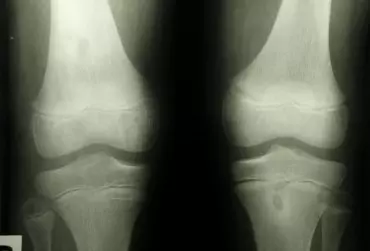

Leczenie chorej chrząstki stawowej kwasem hialuronowym

Wiskosuplementacja, czyli dostawowa iniekcja kwasu hialuronowego, ma przede wszystkim na celu asekurację powierzchni stawowych w celu zapobieżenia pogłębiania zmian już powstałych, a w pewnych przypadkach profilaktykę przed pojawieniem się zmian o charakterze przeciążeniowym. Szczególnie dotyczy to stawów narażonych na maksymalne obciążenia (staw kolanowy) u osób aktywnych sportowo.